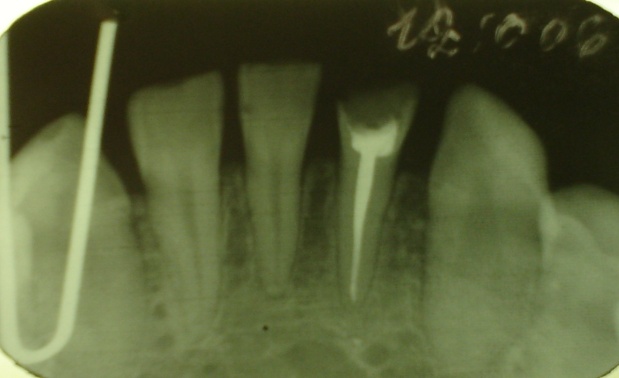

На внутриротовой контактной рентгенограмме удовлетворительного качества в области 42,41,31 зубов определяется дефект коронки 31-го зуба, полость зуба заполнена рентгеноконтрастным пломбировочным материалом, корневой канал запломбирован на всю длину, периодонтальная щель прослеживается на всем протяжении. В области всех зубов определяется деструкция вершин и остеопороз, снижение высоты межзубных перегородок.